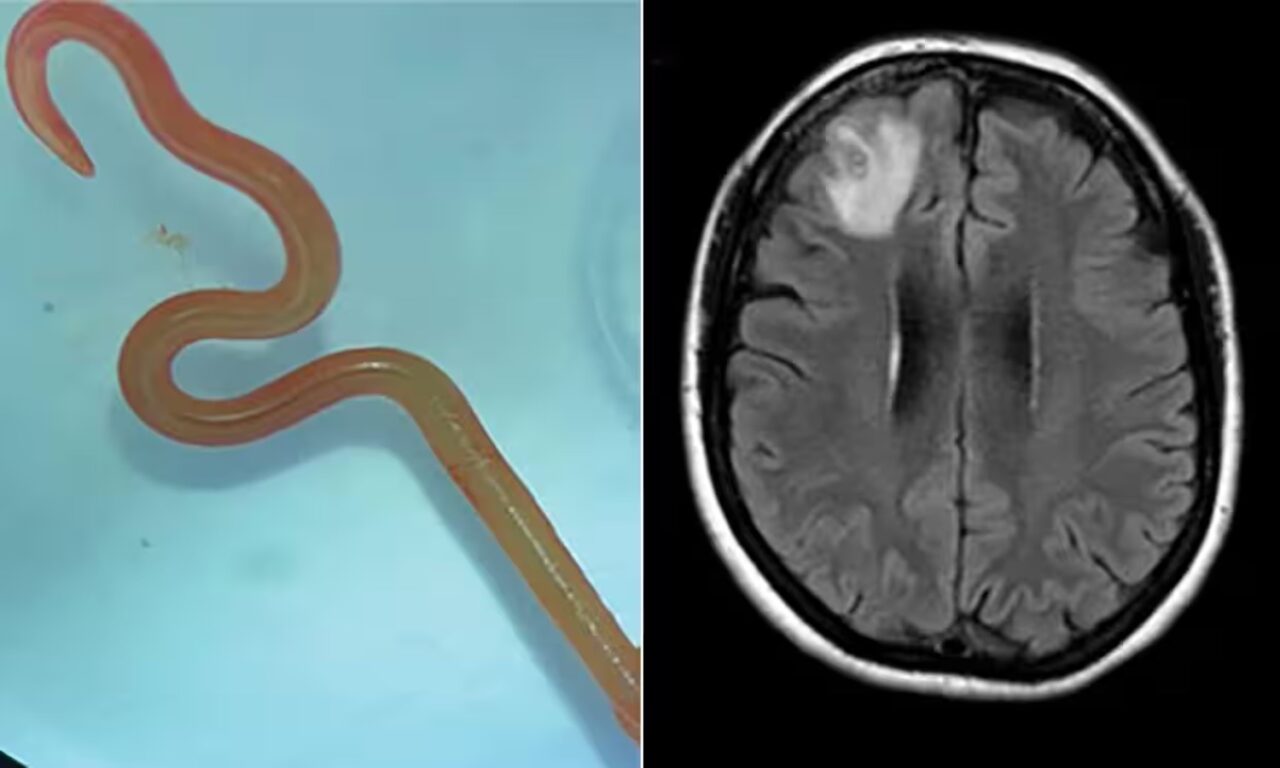

Nel Regno Unito i medici hanno trovato una tenia nel cervello di un uomo di 50 anni . Per 4 anni il paziente ha sofferto di mal di testa, convulsioni, flashback e percepiva strani odori. Fino a quando, nel 2012, medici hanno rimosso un verme che era penetrato da un lato all’altro del suo cervello. Il verme è stato scoperto dopo che le immagini della risonanza magnetica hanno rivelato un insolito gruppo di anelli che si muovevano attraverso il suo cervello. Gli scienziati, come hanno riportato sulla rivista Genome Biology, hanno successivamente scoperto che si trattava di un tipo di tenia nota come Spirometra erinaceieuropaei, che si trova tipicamente negli anfibi e nei crostacei in Cina. I medici responsabili della scoperta hanno affermato che probabilmente l’uomo aveva contratto il parassita durante una visita in Cina, attraverso carne o acqua contaminata. Hayley Bennett, che lavorò al caso, disse all’epoca: «Gli esseri umani sono ospiti rari e accidentali di questo particolare verme».